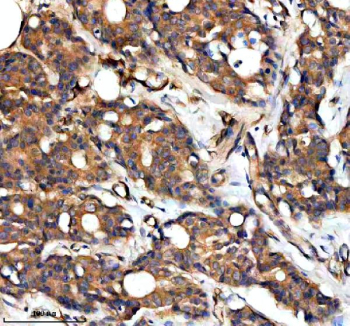

Immunohistochemical staining of RAPH1 using anti-RAPH1 antibody. RAPH1 was detected in a paraffin-embedded section of human liver cancer tissue. Heat mediated antigen retrieval was performed in EDTA buffer (pH 8.0, epitope retrieval solution). The tissue section was blocked with 10% goat serum. The tissue section was then incubated with 2 ug/ml rabbit anti-RAPH1 antibody overnight at 4oC. Peroxidase Conjugated Goat Anti-rabbit IgG was used as secondary antibody and incubated for 30 minutes at 37oC. The tissue section was developed using an HRP secondary and DAB substrate.